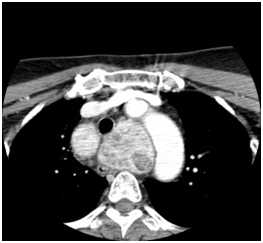

Figure 2 Axial view of mediastinal goiter.

Figure 3 Goiter extend below aortic arch to level of carina